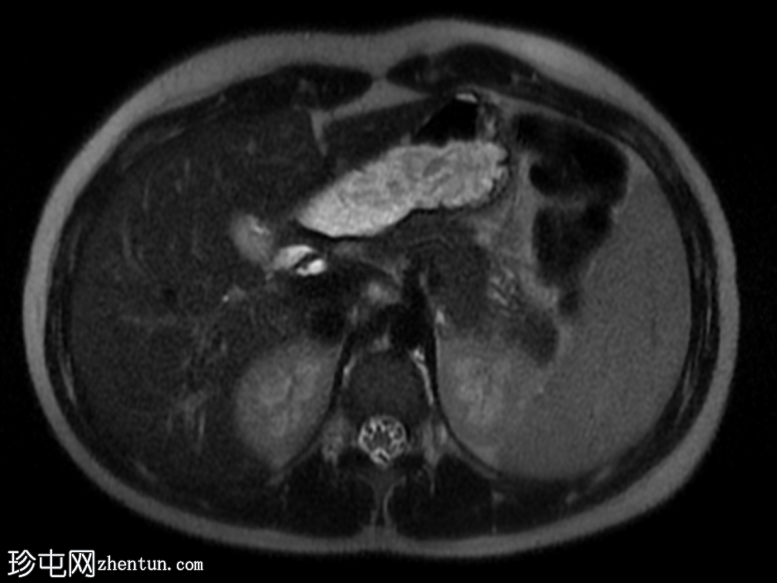

冠状位

T2加权像

子宫前倾位,分区解剖结构正常。矢状位序列可见子宫前壁肌层局灶性边界不清的低信号病灶,但在后续序列中未见明显,符合短暂的生理性子宫肌层收缩表现。

双侧卵巢大小及卵泡活动均正常。未见囊性或实性肿块。

腹部MRI检查结果正常。

该病例的盆腔器官MRI表现与患者年龄(14岁)相符,子宫位置正常,分区解剖结构正常,双侧卵巢大小及卵泡活动均正常,未见囊性或实性肿块。

此外,MRI还意外发现子宫肌层局灶性病变,T2信号低,易被误诊为子宫肌瘤。然而,该病变在后续序列中消失,符合短暂的生理性子宫肌层收缩所致。